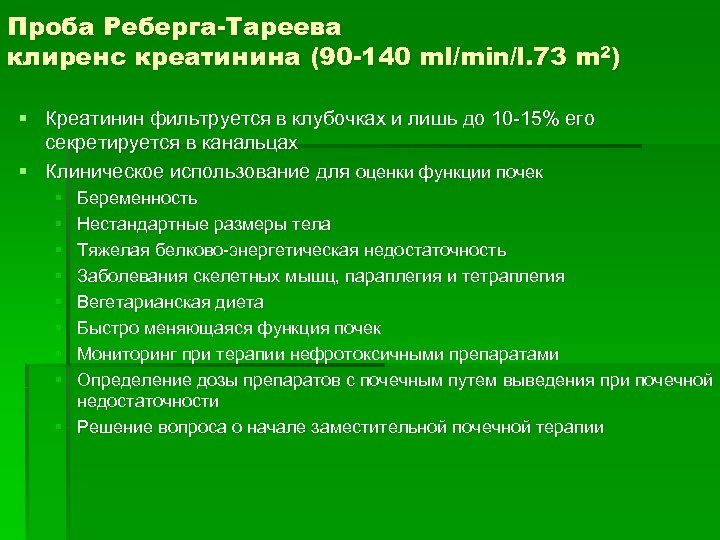

Проба Реберга-Тареева клиренс креатинина (90 -140 ml/min/l. 73 m 2) § Креатинин фильтруется в клубочках и лишь до 10 -15% его секретируется в канальцах § Клиническое использование для оценки функции почек § § § § Беременность Нестандартные размеры тела Тяжелая белково-энергетическая недостаточность Заболевания скелетных мышц, параплегия и тетраплегия Вегетарианская диета Быстро меняющаяся функция почек Мониторинг при терапии нефротоксичными препаратами Определение дозы препаратов с почечным путем выведения при почечной недостаточности § Решение вопроса о начале заместительной почечной терапии